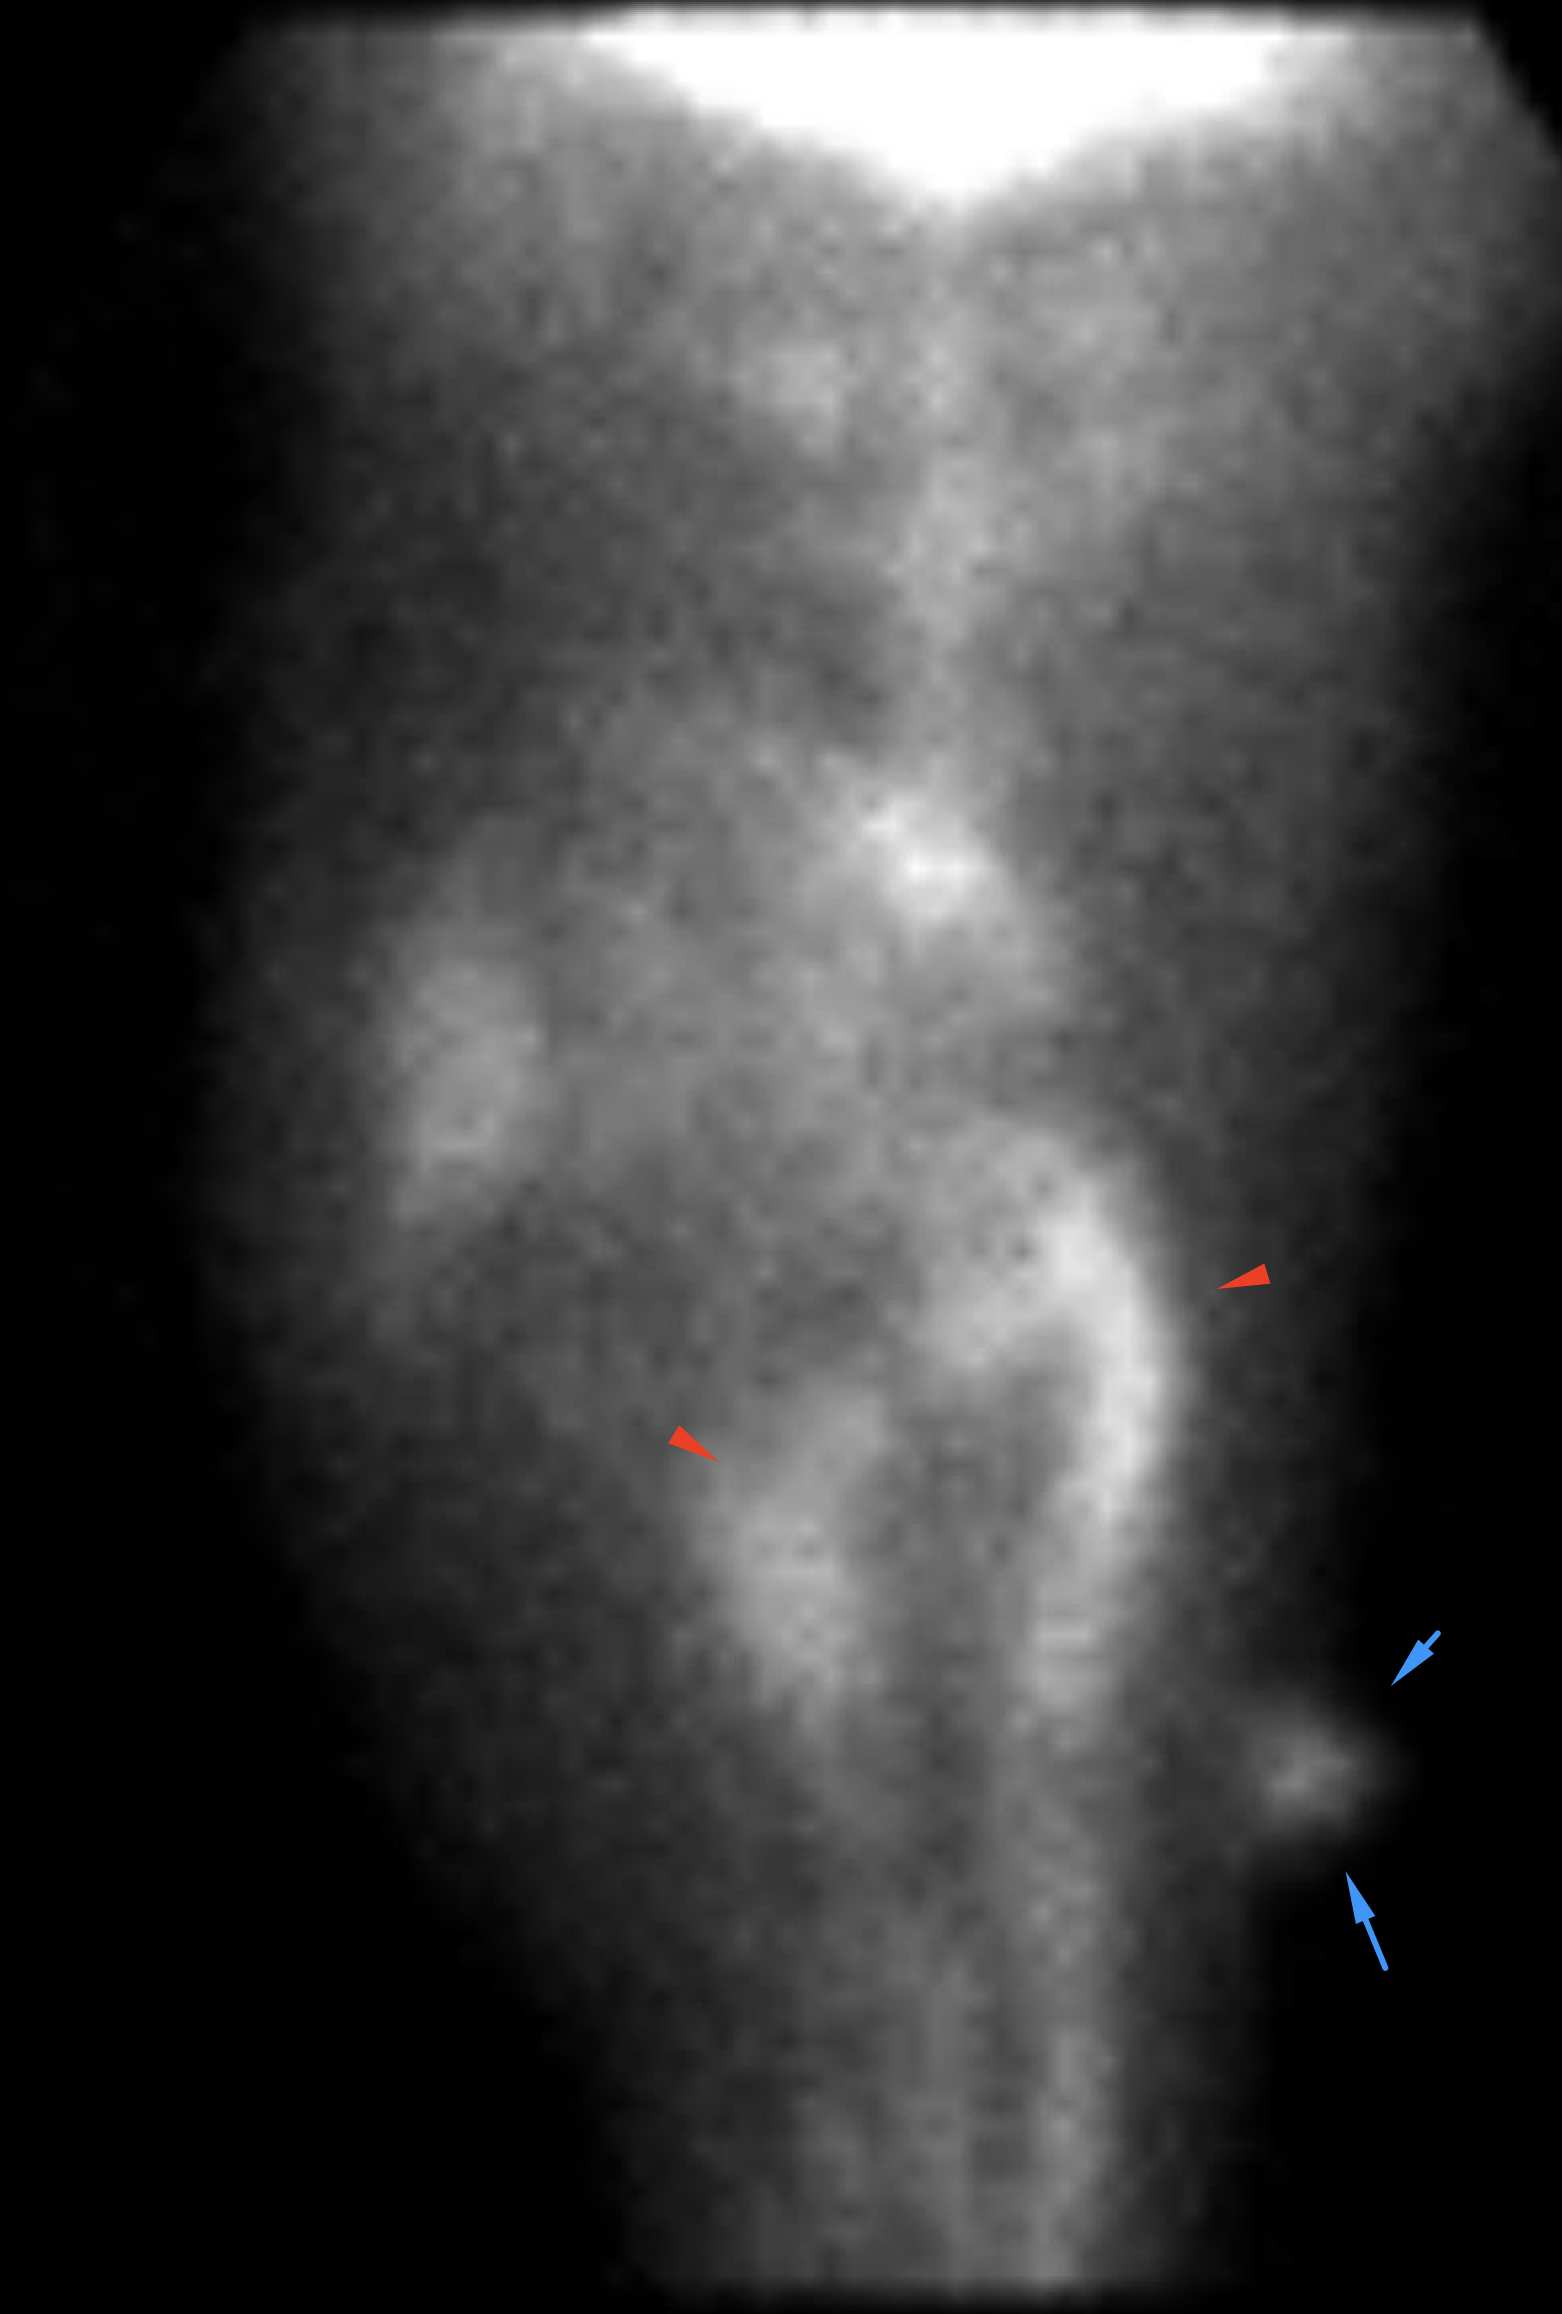

Age: 93

Sex: Male

Indication: Hematochezia

Radiotracer: Tc99m labeled RBCs

Sample ReportNo evidence of active GI bleeding during the course of this study.